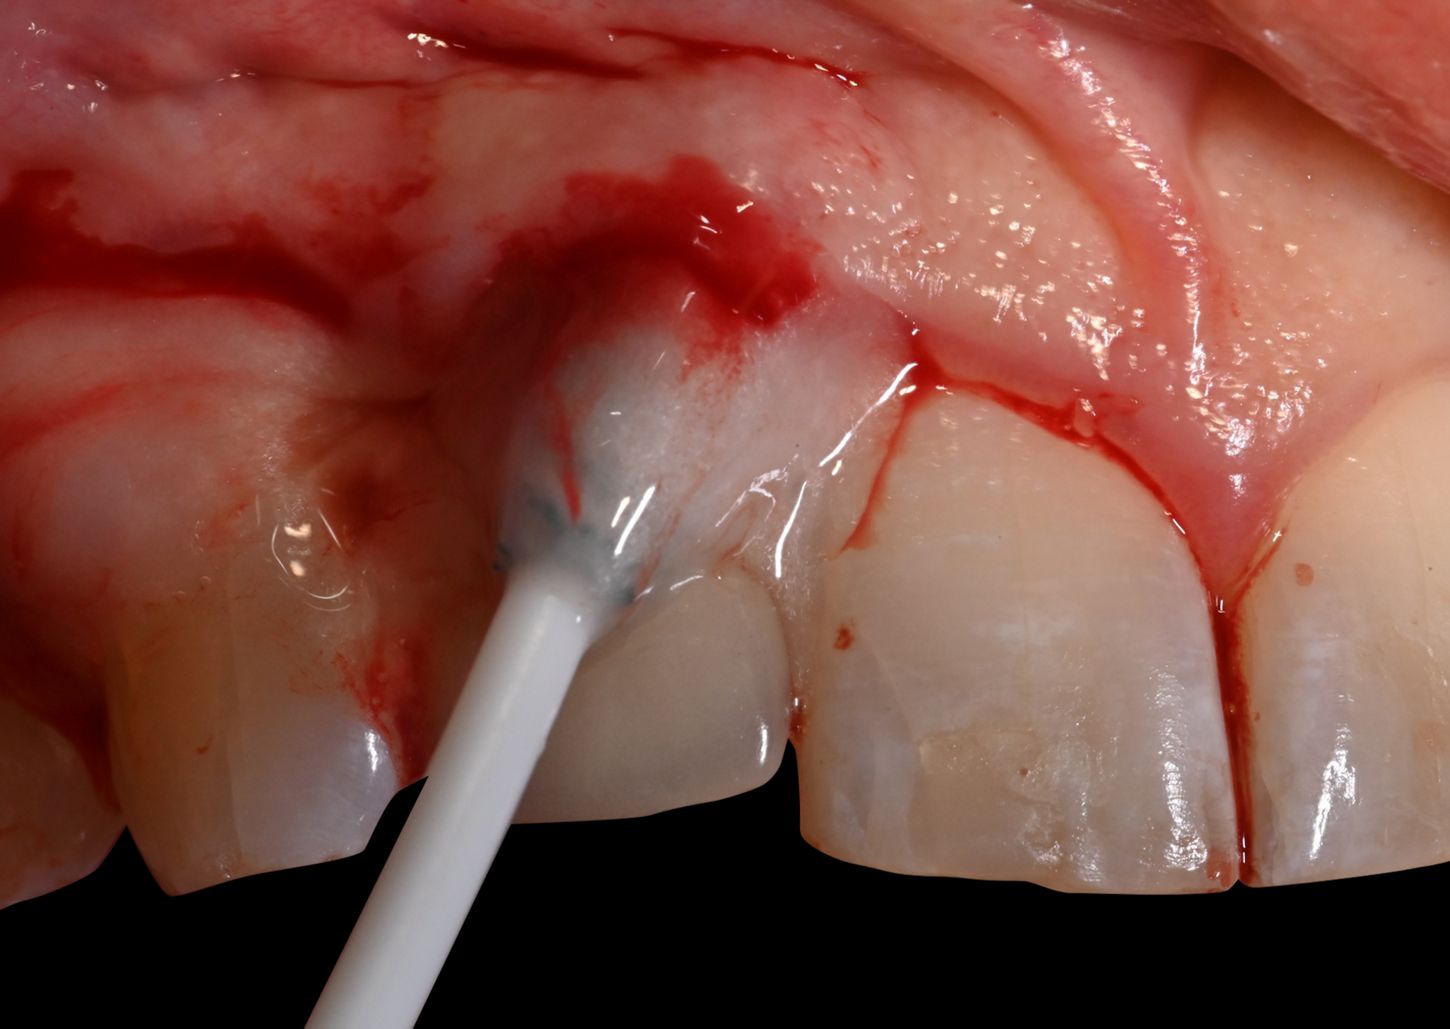

After local anesthesia with Xylocaine Dental Adrenaline (Xylocaine 20 mg/ml + epinephrine 12.5 μg/ml) an intracrevicular incision was placed circumferentially around the implant and papillae and extended to the line angles of tooth 13 and 11. A full-thickness mucoperiosteal flap was raised, and the implant with osseous defect was exposed and examined. Open flap debridement with removal of granulation tissue and calculus on the implant surface was performed with a titanium curette. After irrigation of the defect with sterile saline, the implant was debrided with Labrida BioClean™ soaked in Straumann® PrefGel® for approximately two minutes, followed by irrigation with sterile saline solution and the application of Straumann® EMDOGAIN® starting from the base of the defect.